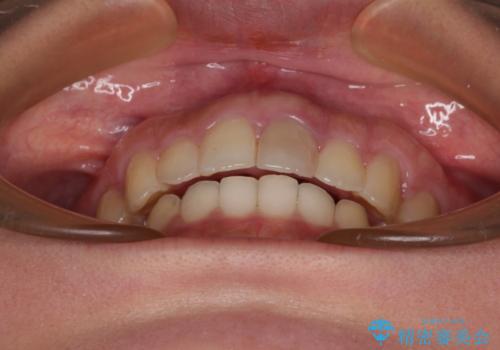

飛び出した上顎前歯 インビザラインで引っ込める

- 前歯の突出感を気にして来院された患者様です。

奥歯の咬み合わせは理想的な咬合に近く、インビザラインでも十分に対応できる歯列でした。

舌の突出癖を改善するためのトレーニングを行いつつ、上下歯列全体を後方に移動させ、更にはIPR(歯と歯の間を削る)によりスペースを獲得することで、口元の突出感を改善することとしました。

治療途中に上顎前歯が歯髄壊死を起こし、変色してしまいました。

痛みを感じたらすぐに連絡いただくよう伝えていましたが、忘れてしまっており、痛みと変色が発現したことで、すぐに連絡することを思い出されたとのことでした。

今後は、根管治療を行った後に、オールセラミッククラウンにて補綴治療を行う予定です。